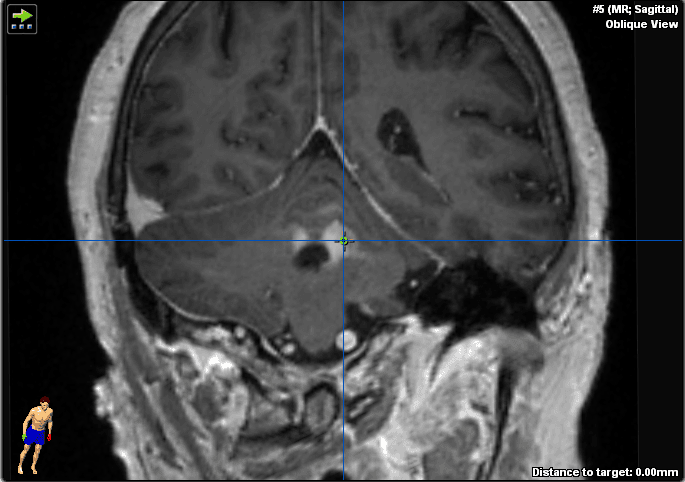

Ha effettuato una risonanza magnetica che ha mostrato una lesione omogenea con contrasto adiacente al quarto ventricolo nel tessuto cerebellare e un edema perifocale moderato (Figure 1–2). I peduncoli del tronco encefalico e cerebellari non erano coinvolti. Non sono stati rilevati segni di emorragia o ischemia.

Figura 1. Queste immagini ponderate T1 potenziate dal gadolinio mostrano una lesione infratentoriale nel cervelletto e nel peduncolo cerebellare sinistro adiacente al quarto ventricolo. Si prega di notare l'aumento omogeneo del contrasto sospetto di linfoma del SNC e mancanza di infiltrazione del tronco encefalico.